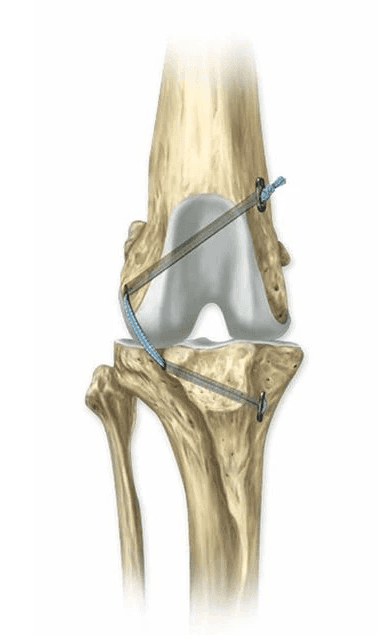

Tibial Plateau Leveling Osteotomy (TPLO):

This procedure aims to stabilize the knee by changing the biomechanics. It involves making a semicircular cut in the tibia then rotating the piece so the angle between the femur and tibia is nearly level. This eliminates the need for the CrCL and restores stability.

Conceptually, you can think of this like a 'wagon on a hill'. The wagon will remain in place with a rope tether (CrCL). However, if that is cut, then the wagon will roll down the hill. Following the TPLO, the 'wagon' sits on a flat surface, eliminating the abnormal movement.

The fragments are then stabilized with a bone plate and screws. The bone typically heals in 6–10 weeks, during which strict activity restriction is essential.